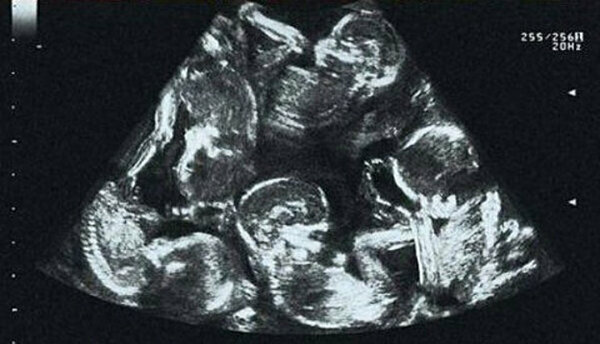

Aleksandra Kinova, když zjistila, že je těhotná, byla s tak dobrou zprávou neuvěřitelně šťastná. Těhotenství bylo perfektní, protože žena byla mladá a zdravá. Aleksandra se svým stavem zacházela velmi opatrně a něžně, a když na prvním ultrazvuku zjistila, že má v břiše více než jedno dítě, na tyto zprávy reagovala klidně, protože už měla dvojčata z předchozího těhotenství. Ona a její manžel byli rádi, že byli rodiči několika dětí najednou. Jak se však ukázalo, na pár čekaly zcela neobvyklé zprávy. Jak těhotenství postupovalo, lékaři si všimli, že žena bude mít čtyři děti! Ale i tehdy se Aleksandra ukázala klidná, nedělala si starosti, ale rozhodla se pečlivěji a důkladněji se připravit na nadcházející porod.

Žena podstoupila všechny naplánované testy. Během jedné z těchto relací však nový objev vyšel zcela nečekaně! Lékaři již spočítali pět dětí.

Aleksandra tomu nemohla uvěřit a vykřikla. Ne ze strachu, ale ze štěstí. Koneckonců, ne každá žena je vybrána vesmírem pro takovou misi - pět dvojčat se rodí pouze jednou za několik století.

Narození těchto dětí sledovala celá země, protože podle statistik provedených od roku 1949 nebyl takový případ nikdy zaznamenán. Aleksandra porodila 4 syny a 1 dceru, kteří byli jmenováni: Daniel, Michael, Martin, Alex a Tereza. Rodiče kvintupletů dostaly mnoho blahopřání a darů od obyvatel České republiky i od státu.